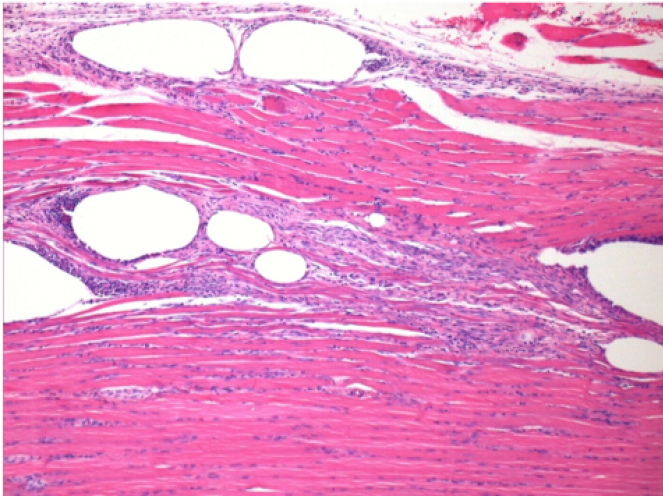

Iniezione Endopeel nel tessuto subcutaneo SC

Scatola 6

0.5 ml ( 5x 0.1ml): Iniezione SC di Endopeel nel tessuto pretibiale subcutaneo SC destro (Dx).

Sx:200x-Controllo-SC

Dx-Giorno10-SC-200X

Dx-Giorno30-SC-200X

Dx-Giorno90-SC-200X

Dx-Giorno210-SC-200X

Dx-Giorno210-SC-400X

Endopeel induce una miofibrolisi selettiva reversibile e una risposta infiammatoria approssimativamente nel periodo di 1 mese.

I cambiamenti dei tessuti muscolari sono quasi completamente reversibili.

Il muscolo é il posto migliore per iniettare Endopeel ,per la sua maggiore efficacità, il controllo e la durata della sua azione.

Nessuna necrosi ne ascesso sono stati osservati durante la sperimentazione.